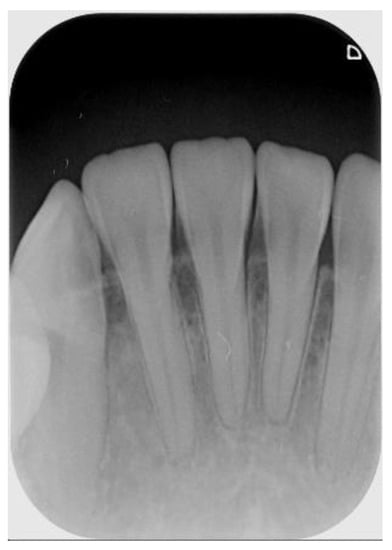

Table 4 shows that the larger the indicators the better is the accuracy. Table 4 also shows that the indicators in the proposed model are larger than that of the previous work in [23]. Consequently, the CNN image identification ability should be excellent especially in clinical medicine thus the need for high-precision judgment to provide better medical quality. The actual application of this technology uses the clinical images of Figure 7 and Figure 8 as the target image for judging the symptoms. After implementing this technology, the results are shown in Table 5 and Table 6.

Figure 7. Outer example for validation (number 1 to 5 from left to right).

Table 5. Result after judgement for Figure 7 sample image.

Figure 7

Number

Clinical DataThis Study

1Normal99.6% to be normal

2Normal99.8% to be normal

3Normal98.6% to be normal

4Normal99.9% to be normal

5Normal99.9% to be normal